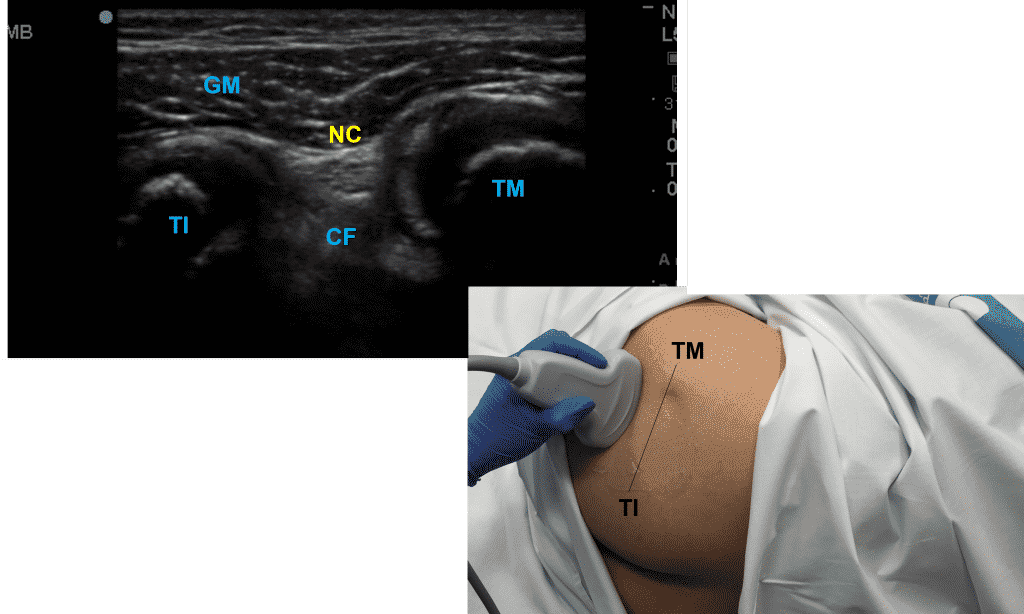

Localización ecográfica: A nivel glúteo, identificaremos dos referencias óseas, la tuberosidad isquiática (TI) a nivel medial y el trocánter mayor (TM) a nivel lateral. Tras identificarlas, uniremos dichas referencias por medio de una línea y localizaremos el punto medio. Colocaremos nuestra sonda en esta línea y nos deslizaremos a lo largo de ella para identificar las distintas estructuras que nos ayudaran en la localización del nervio ciático, el cual encontraremos entre los músculos glúteo mayor (GM) y cuadrado femoral (CF).

Paciente en posición de Sim que permite la localización del trocánter mayor (TM) y de la tuberosidad isquiática (TI). Colocaremos la sonda convexa en el punto medio de la línea trazada entre dichas estructuras, visualizando el nervio ciático (NC) entre ambas y en relación con los músculos glúteo mayor (GM) y cuadrado femoral (CF).